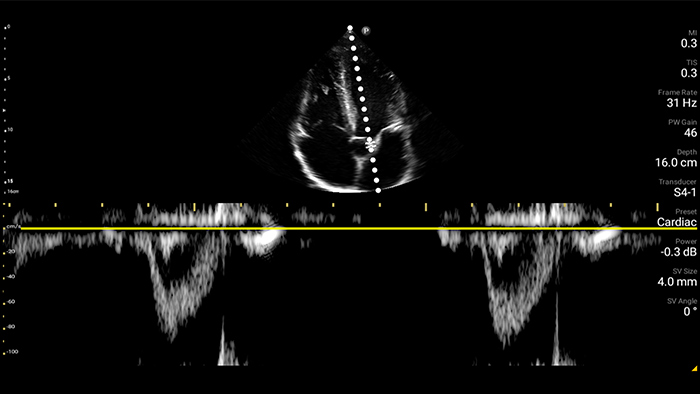

Transductor de disposición en fase de banda ancha Lumify S4-1

• Rango extendido de frecuencias de operación de 4 a 1 MHz • 2D, Doppler a color, Modalidad M, XRES avanzado e imágenes armónicas multivariables • Imagenología de alta resolución para aplicaciones abdominales y cardíacas: optimizaciones de preajustes de imágenes cardíacas, gineco-obstétricas, pulmonares, abdominales y FAST.

Ultrasonido cardíaco en el punto de atención prehospitalario: embolia pulmonar